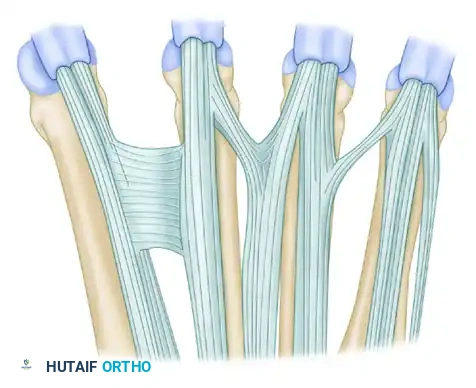

FIGURE 66-62: Most common pattern of extensor tendons on the dorsum of the hand, illustrating the single EIP, single EDC to index and long fingers, double EDC to the ring finger, absent EDC to the small finger, and double EDQ.

Extensor indicis proprius (EIP) anatomy, demonstrating its classic ulnar relationship to the EDC of the index finger.

The Juncturae Tendinum

The juncturae tendinum are intertendinous connections located proximal to the metacarpophalangeal (MCP) joints. They serve a vital biomechanical role by coordinating digital extension and distributing forces across the dorsal hand. However, they also act as a double-edged sword in trauma, as they can mask complete tendon lacerations.

FIGURE 66-63: Overview of the Juncturae Tendinum classifications.

The juncturae are classified into three primary types based on their morphology and location:

Type 1 (Thin Filamentous Type):

Found predominantly between the EDC tendons of the long (EDC m) and index (EDC i) fingers. Notably, these juncturae do not connect to the EIP tendon. They are present in the second and third intermetacarpal spaces.

Type 2 (Thicker Type):

These are thicker, more robust connections found between the EDC tendons of the ring (EDC r) and long (EDC m) fingers. They are located exclusively in the third and fourth intermetacarpal spaces.

Type 3 (Subtype y):

In this variation, a Y-shaped tendon and juncturae appear as a split tendon inserting into two adjacent digits. This is most commonly seen between the EDC tendons of the ring (EDC r) and long (EDC m) fingers.

Type 3 (Subtype r):

This is a more oblique, R-shaped junctura between the EDC to the ring finger (EDC r) and the most radial of the three EDQ tendons to the small finger.

Additional anatomical variations and interconnections of the dorsal extensor mechanism are illustrated below, highlighting the complexity surgeons must navigate during dorsal hand reconstruction: